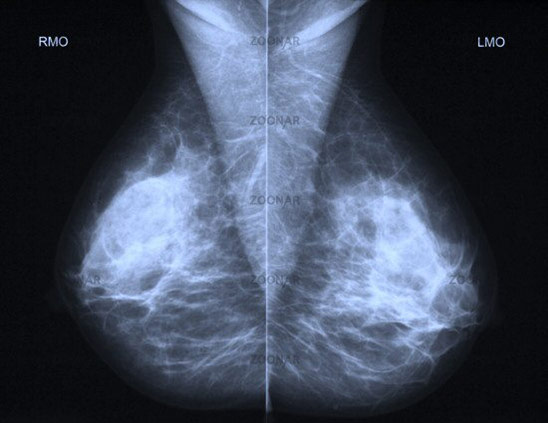

A sample mammogram / breast image.